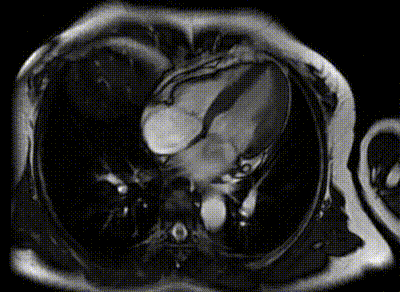

(四腔心电影序列)